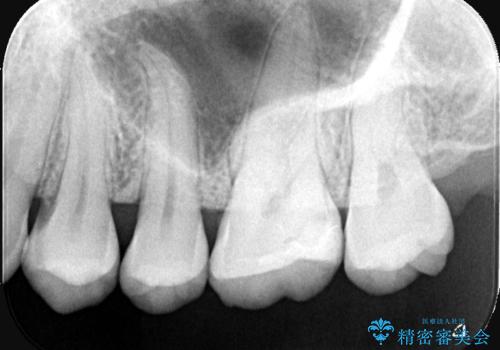

咬合面に穴が空き、歯の中でう蝕が広がっていました。この歯が過去に咬合面う蝕を経験しCR修復を受けていること、今回歯質とCRの境目からの二次う蝕になっていることを説明し、適合や材料安定性の良いセラミックインレーでのやり替えとなりました。

セット時はラバーダム防湿を行っています。